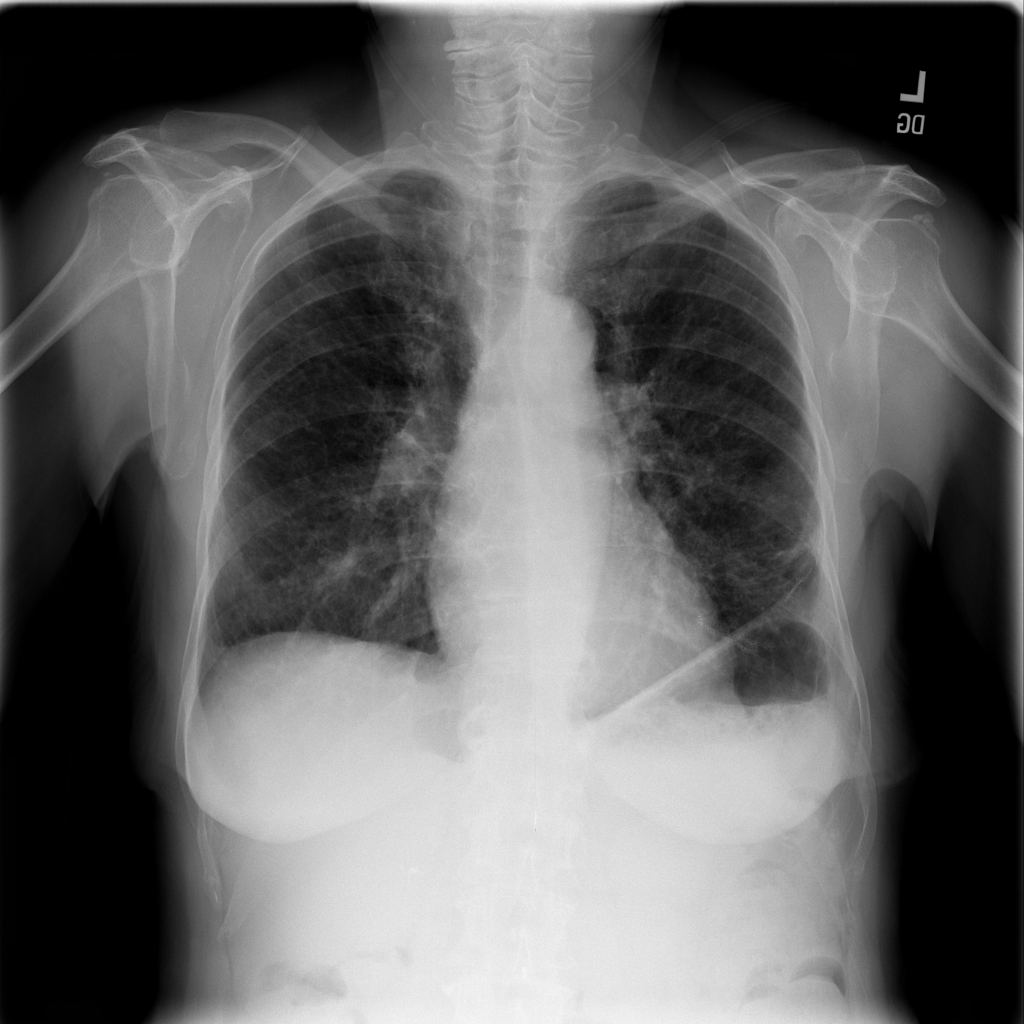

PAT-1F50 · IMG-000Fibrosis

PAT-1F50 · IMG-000

PA